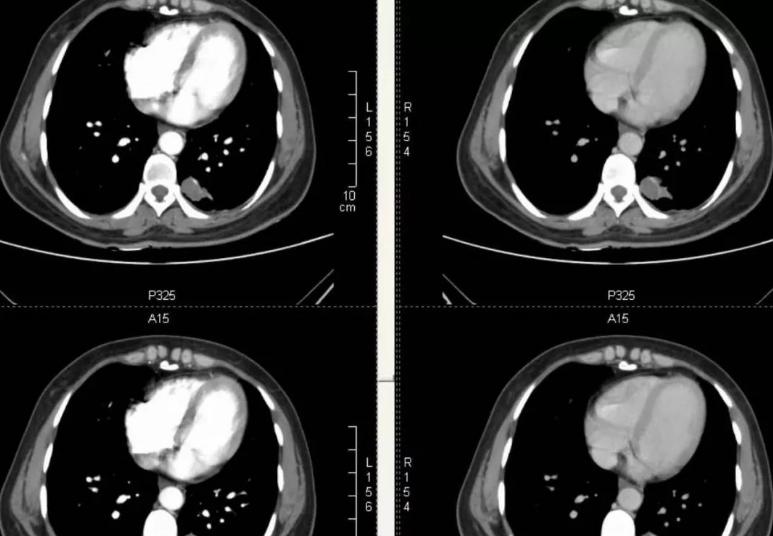

就抓紧在家人的带领下到医院进行检查,医生一看检查结果:原本是之前手术处理过的血管,这又快堵上了。